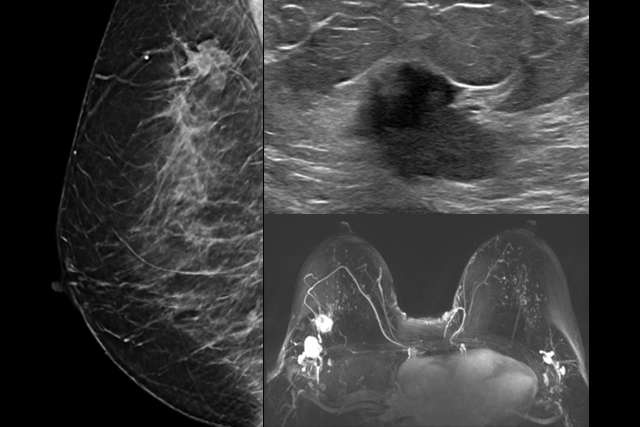

BIRADS:

Mammography

MRI

Ultrasound

Learn how to use BI-RADS terminology to interpret Mammograms, MRIs, and Ultrasound cases.